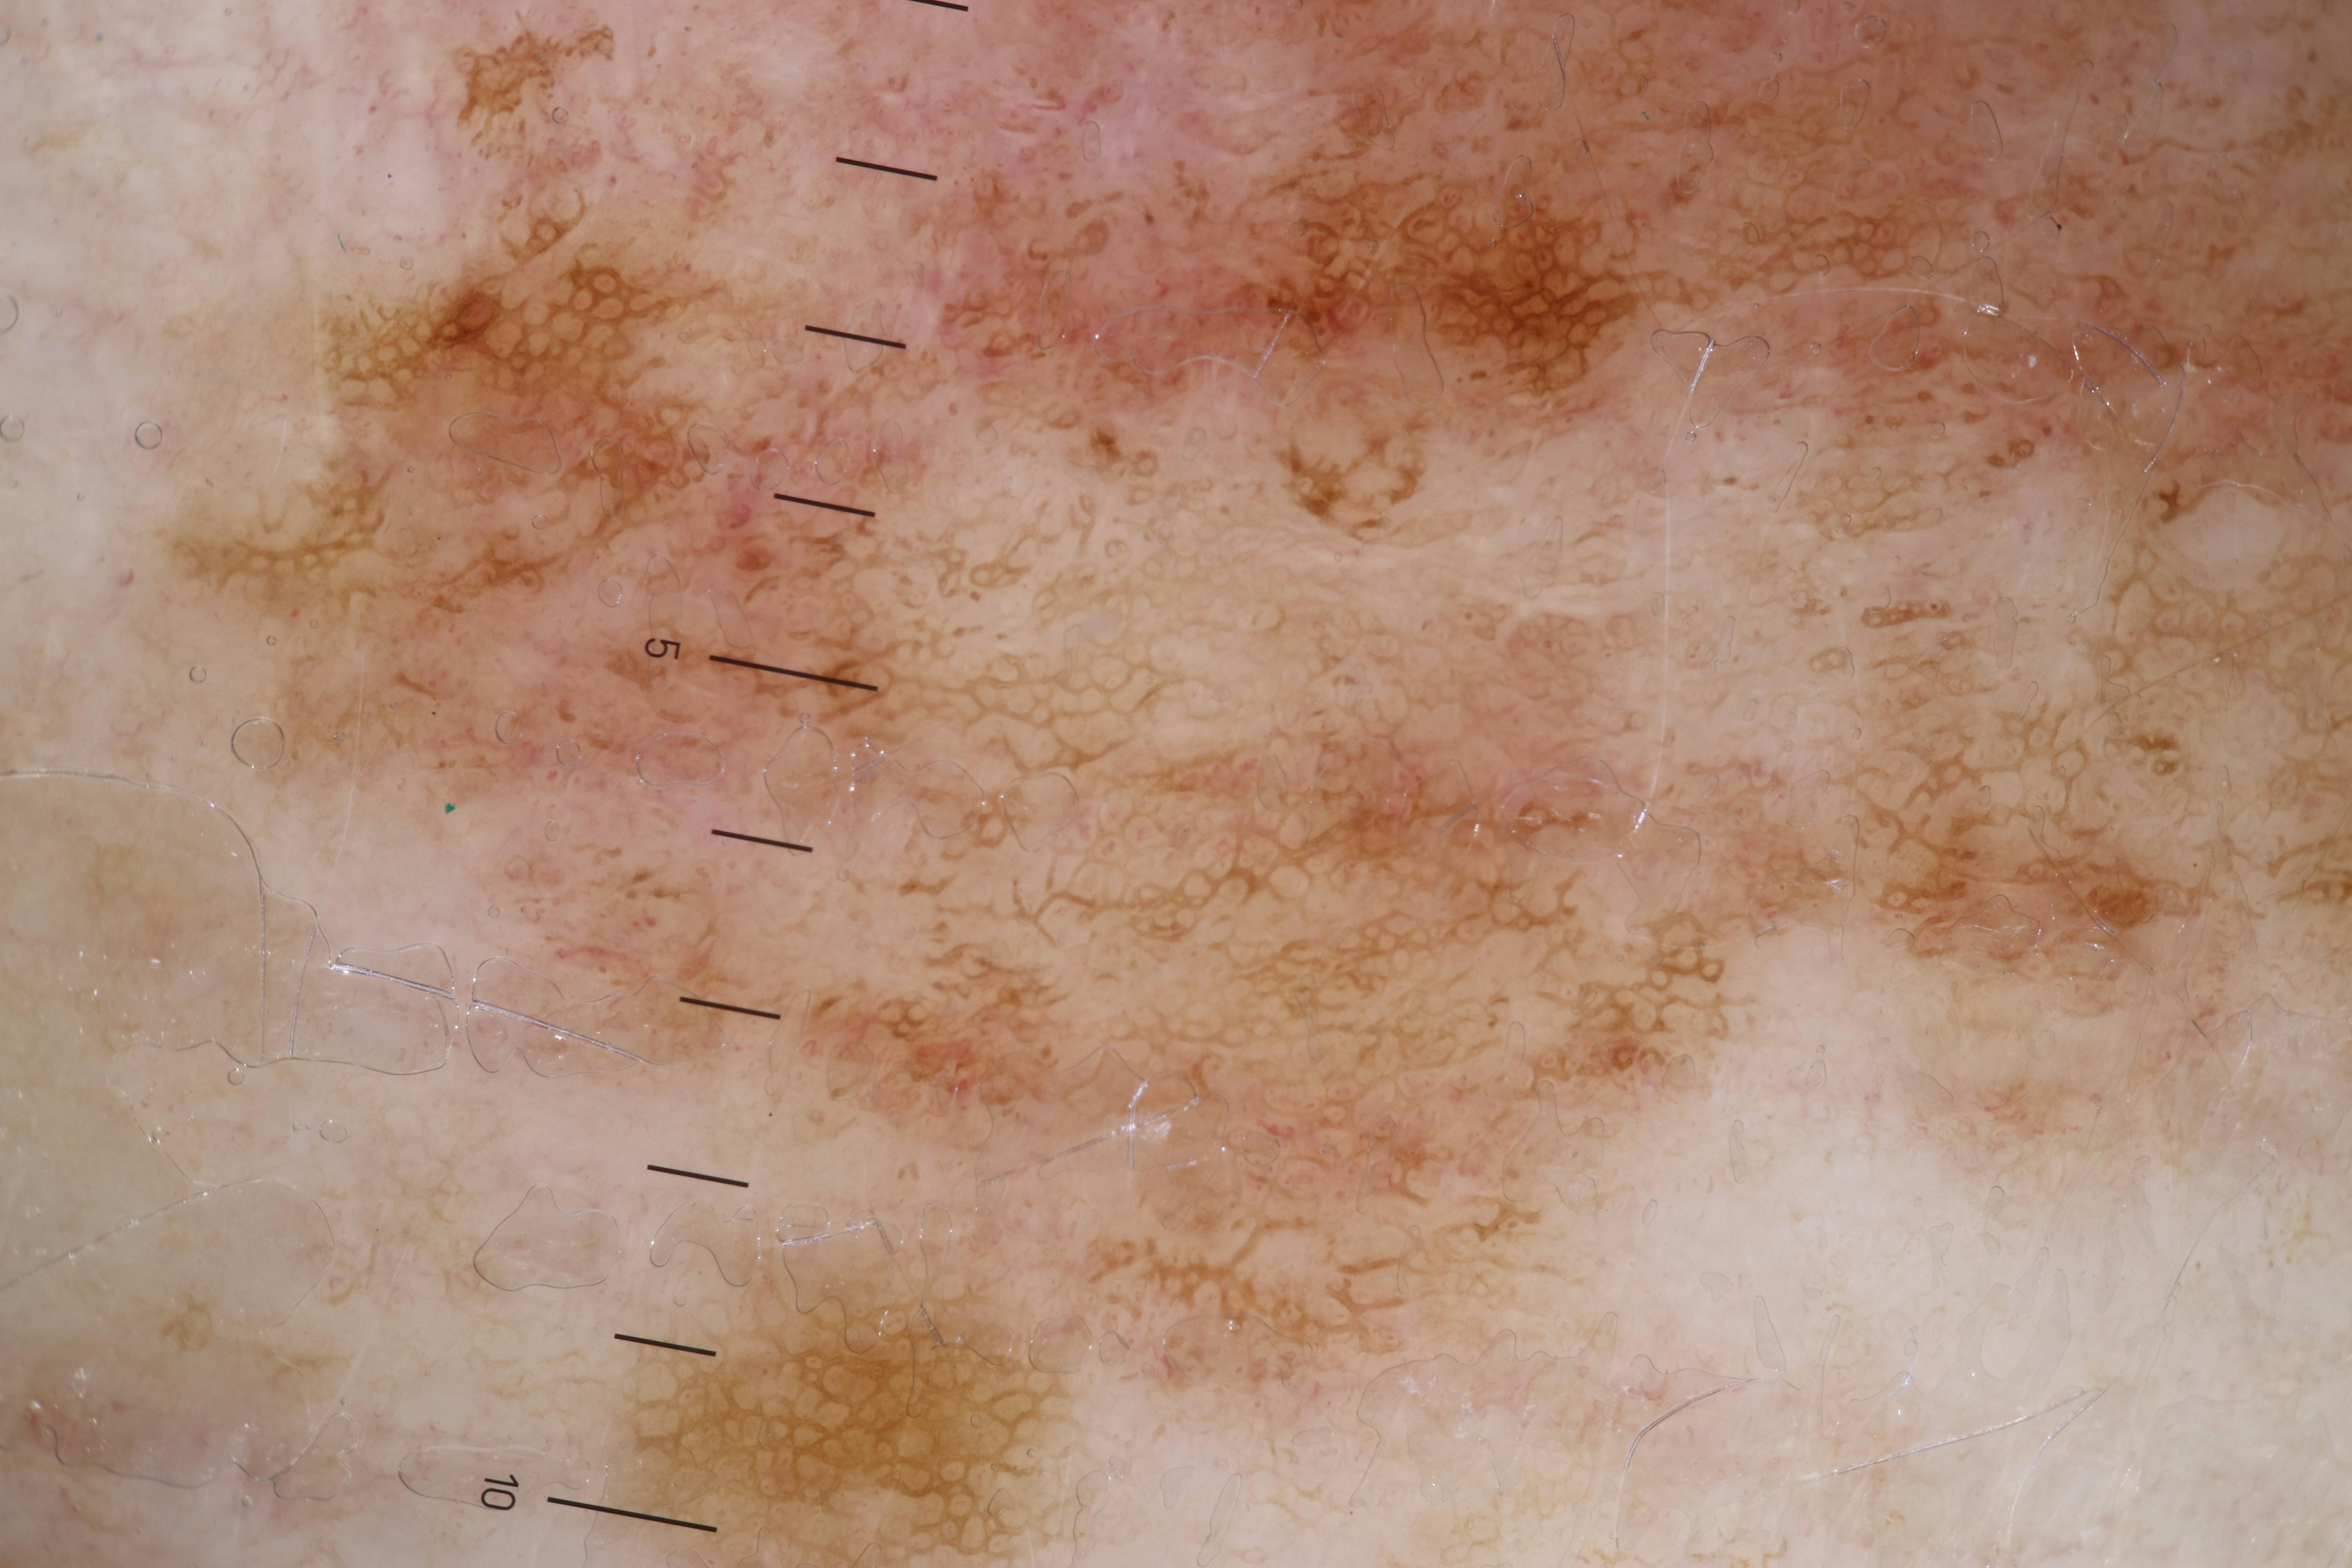

{

"acquisition_day": 820,

"age_approx": 55,

"anatom_site_general": "lower extremity",

"concomitant_biopsy": false,

"diagnosis_1": "Malignant",

"diagnosis_2": "Malignant melanocytic proliferations (Melanoma)",

"diagnosis_3": "Melanoma, NOS",

"diagnosis_confirm_type": "histopathology",

"fitzpatrick_skin_type": "II",

"image_type": "dermoscopic",

"lesion_id": "IL_2723500",

"melanocytic": true,

"patient_id": "IP_8675890",

"sex": "male"

}